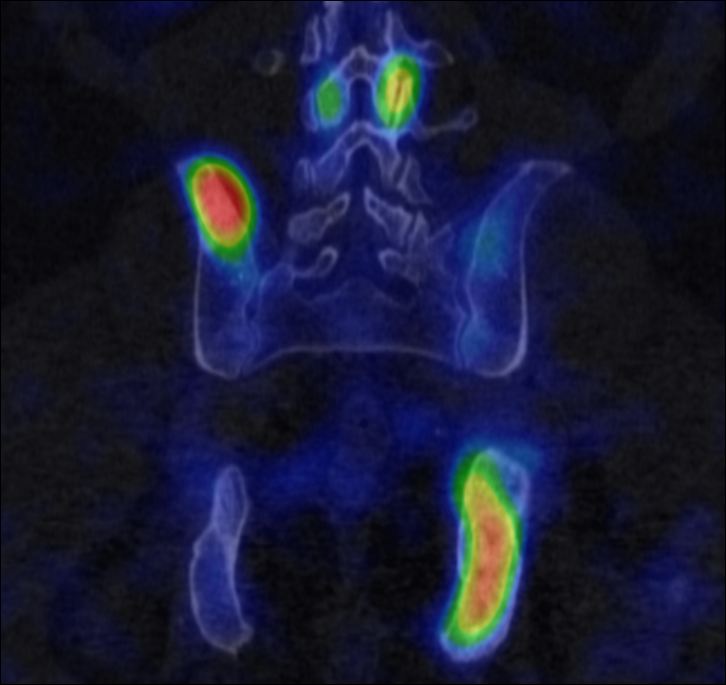

More complex anatomic structures (spine, the base of the skull, facial and hip bones) can be imaged more confidently with SPECT scans. On one hand, they provide a more accurate spatial localization and on the other, with their superior contrast resolution, they are able to differentiate lesions even if planar exams are negative or uncertain. SPECT-CT can characterize the CT morphology of the lesions with pathologic uptake. Thus, it is capable to provide a definitive diagnosis. (Figure 4.)

Image

a

b

c

d

e

4. Bone scintigraphy, prostate cancer. The image set shows the characterization of multiplex increased activity uptake. Posterior whole body scan (a). SPECT-CT coronal fusion images (b,d), CT examination (c,e). Sclerotic lesions in the pelvic bones are suggestive of osteoplastic metastases (b,c), small joint arthrosis at LIII-IV segments, more expressed on the left side (b,c), spondylosis on the right side at LIV-V segments (d,e). (The increased activity spot on the whole body scan, at the left cubital region, is correspondent to the paravasation of the iv. radiopharmaceutical.)